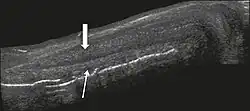

Figure 2: Longitudinal section of the penis under right lateral access. Note the cylindrical structure, corresponding to the corpus cavernosum (thick arrow), in the superior portion and the corpus spongiosum (thin arrow), adjacent to the corpus cavernosum, in the inferior portion.[1]

The corpora cavernosa are homogeneous and relatively hypoechoic cylindrical structures lined with tunica albuginea, a thin membrane that has a thickness of approximately 2 mm when the penis is flaccid and 0.25 mm when it is erect. The corpus spongiosum, a ventral, medial body that is more echoic than the corpora cavernosa, is also covered by the tunica albuginea and contains the urethra. As can be seen in Figures 1 and 2, it is more dilated and prominent in its proximal segment, known as the bulb, and in its distal segment, constituting the glans. Buck's fascia is superficial to the tunica albuginea and covers all of the structures described.[1]